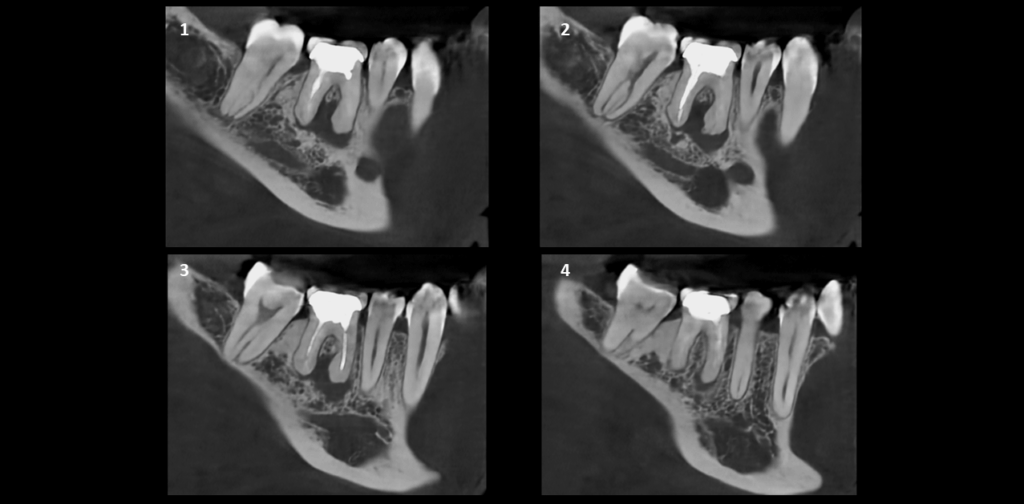

CORTES TRANSAXIALES

CORTES TANGENCIALES